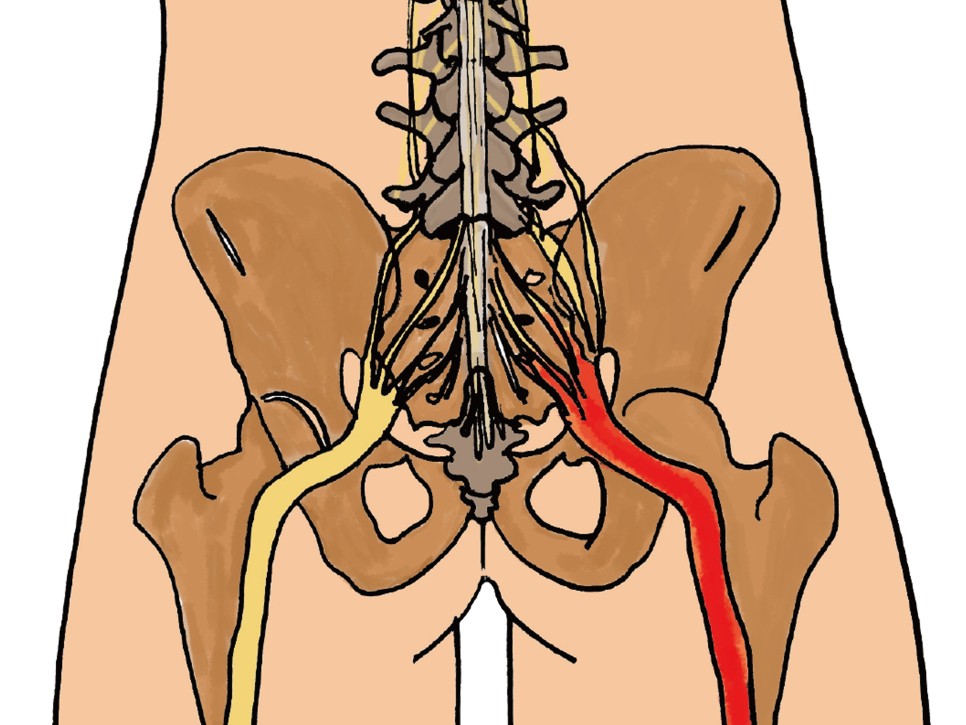

좌골은 의자에 앉았을 때 바닥에 닿는 부위이고 좌골신경은 좌골 안쪽을 지나 다리에 연결되는 신경근이 모인 말초신경입니다. 좌골 신경통은 허리와 엉덩이에서 다리로 이어지는 통증을 말합니다.

좌골신경통이 발생하는 원인은 90% 이상이 디스크로 인해 신경이 눌려 발생하며, 기타 척추관협착증, 이상근증후군, 종양으로 인해 발생할 수 있습니다.

좌골신경통은 꼬리뼈와 천골 사이에 붙어서 고관절골로 이어지는 이상근과 관계가 있을 수 있습니다. 이상근증후군은 좌골신경통의 증상 중 하나로, 신경이 엉덩이에 눌려 종아리와 다리까지 통증이나 감각 이상이 발생합니다.